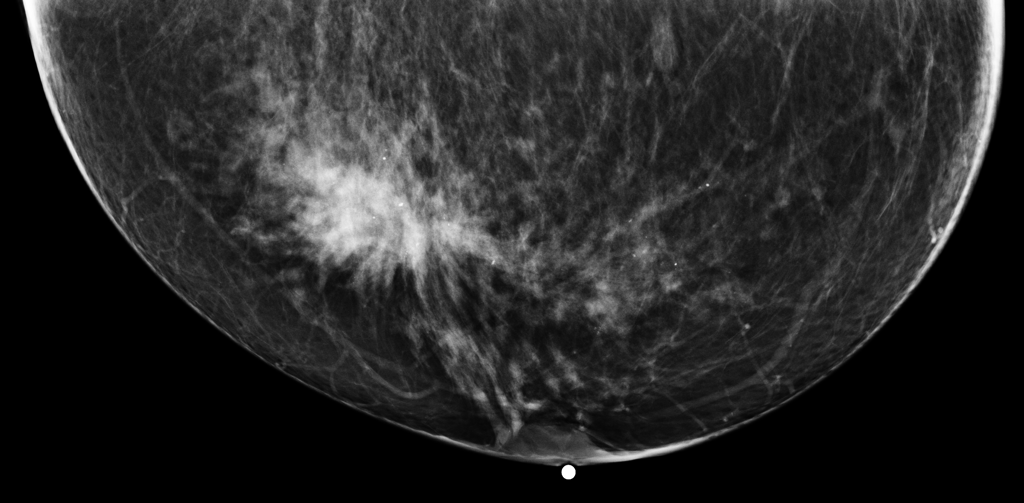

We selected four representative examples, two correctly classified and two misclassified, to qualitatively examine GPT-5’s decision-making in BI-RADS density assessment and malignancy detection tasks. These cases illustrate the model’s strengths in recognizing prototypical imaging features and its weaknesses in borderline density categorization and atypical lesion interpretation, shown in

Table 6: Representative GPT-5 predictions: two correct and two incorrect cases in BI-RADS density and malignancy classification.

Correct: Malignancy (Yes) Correct: Malignancy (Yes) Error: Density D\rightarrowC Error: Malignancy B\rightarrowA

GT: D

Pred: C

Rationale: The breast shows large regions of fibroglandular tissue with some interspersed fat—heterogeneously dense, not almost entirely fatty (A/B) nor uniformly/extremely dense (D).

Error cases (MM-4307, MM-20757): For density assessment errors, the model consistently misclassified BI-RADS category D (extremely dense) as category C (heterogeneously dense), indicating a tendency to underestimate overall density in highly dense breasts. For malignancy assessment errors, benign structural changes were misclassified as malignant (overdiagnosis), suggesting the model is prone to false-positive interpretations when confronted with architectural distortion or irregular mass margins lacking other corroborating malignant features.